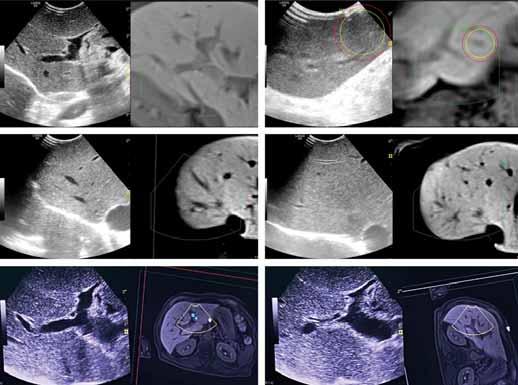

8.1. UNRESECTABLE COLORECTAL LIVER METASTASES

8.2. UNRESECTABLE COLORECTAL LIVER METASTASES